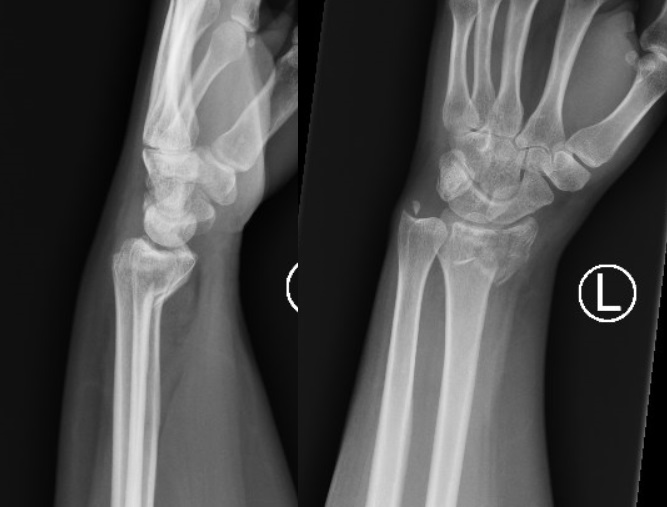

Take a look at the following example. Let us go through how we would systematically analyse this and the diagnosis.

D – This is a … X-Ray taken on ….., of the following patient….. Is there a previous X-ray to compare to

R – Commenting first on the quality, it is not rotated, there is adequate field of view, the projection is AP and lateral and it is adequately exposed as I can see the bones clearly

“On initial inspection, there appears to be a fracture of the distal radius, but I will proceed to go through it systematically.”

B – Looking at the bones first, there is a fracture in the distal radius. It is a closed, simple, transverse fracture. There is dorsal angulation of the distal segment compared to the proximal, but no translation, rotation or shortening. There are no other fractures.

There are no obvious dislocations and the no abnormality in the texture of the bones

D – There are no degenerative changes in the joint spaces

E – There are no other man-made objects or signs of orthopaedic surgery.

In summary, this film shows a fracture of the distal radius with dorsal angulation of the distal segment. This is suggestive of a Colles’ Fracture

Colles’ Fracture